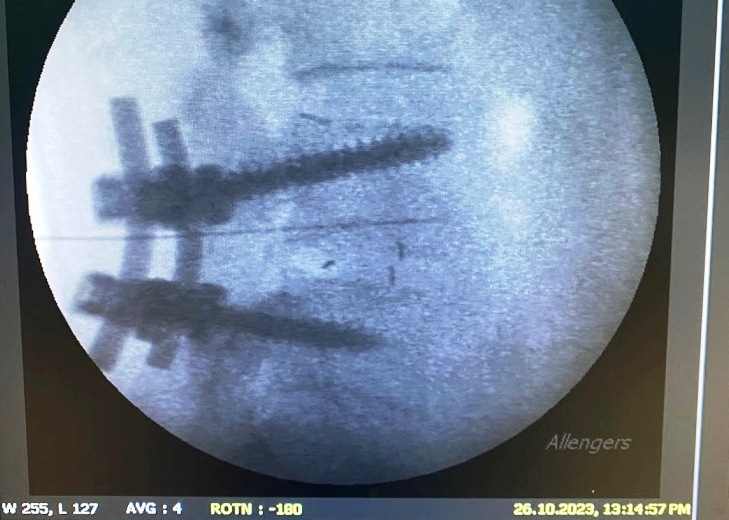

As a compassionate and highly skilled pain management specialist, Dr. Ninadini is committed to the precise diagnosis and multidisciplinary treatment of various pain syndromes. Whether you are coping with chronic back pain, osteoarthritis, or post-operative neuropathic pain, she employs cutting-edge interventional techniques alongside personalized care to deliver optimal therapeutic outcomes.

What is the role of interventional procedures in pain management?

Interventional procedures, such as nerve blocks, radiofrequency ablation, and spinal cord stimulation, play a crucial role in managing chronic pain conditions. These minimally invasive techniques target the source of pain and are often used when conservative treatments are insufficient, providing significant relief and improving the quality of life.